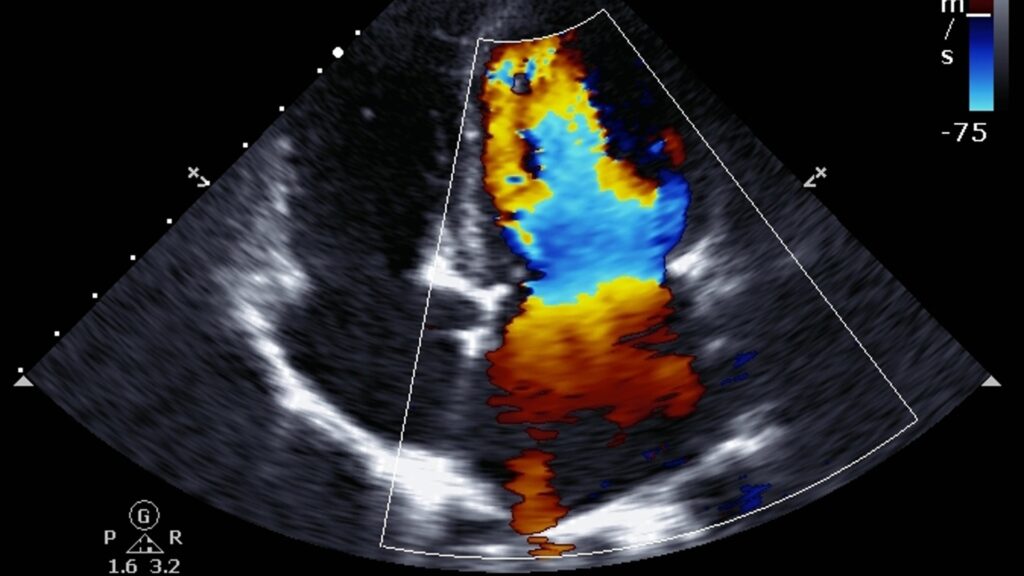

Esse exame utiliza ultrassonografia para criar imagens detalhadas das principais artérias abdominais e medir o fluxo sanguíneo. A técnica Doppler colorido permite visualizar a velocidade e a direção do fluxo sanguíneo, identificando possíveis obstruções e alterações. É frequentemente recomendado para pacientes com dor abdominal crônica, suspeita de isquemia mesentérica ou que possuem fatores de risco cardiovascular.

Durante o exame, você se deita confortavelmente enquanto um gel condutor é aplicado no abdômen. Um transdutor é movido pela pele para capturar imagens detalhadas das artérias. A adição de cores às imagens facilita a visualização do fluxo sanguíneo e ajuda a identificar áreas com fluxo alterado. Este procedimento é realizado por um técnico ou médico especializado em ultrassonografia vascular.

- Avaliação do Fluxo Sanguíneo: Fornece dados detalhados sobre a velocidade e a direção do fluxo sanguíneo, fundamentais para um diagnóstico preciso.